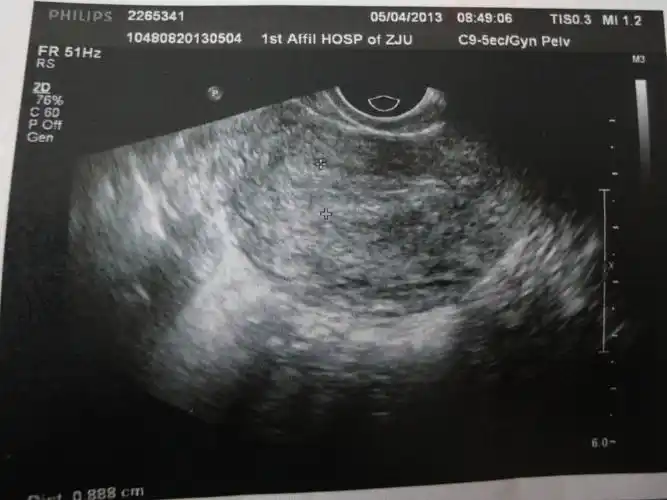

宫腔镜后第一天复查阴超